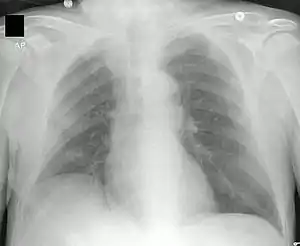

![]() ذات الرئة السفلي الأيمن: يُؤدي التليف الكيسي المُزمن إلى تدمير النسيج البرانشيمي للرئة، مُسببًا في النهاية موت المريض نتيجة لتليف الجهاز التنفسي. ذات الرئة السفلي الأيمن: يُؤدي التليف الكيسي المُزمن إلى تدمير النسيج البرانشيمي للرئة، مُسببًا في النهاية موت المريض نتيجة لتليف الجهاز التنفسي. | |